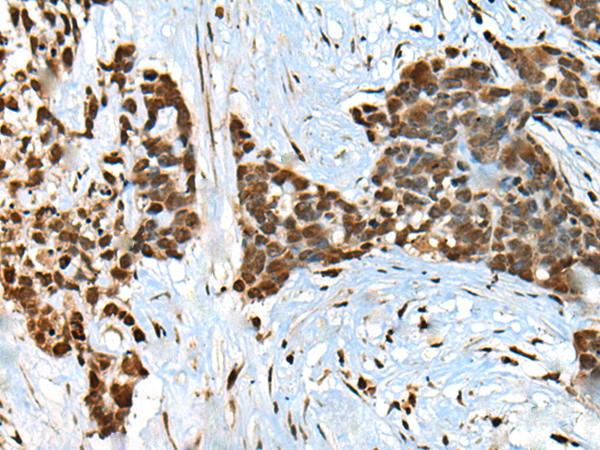

分类: 科研抗体货号: P09446别名:应用: IHC反应种属: Human, Mouse